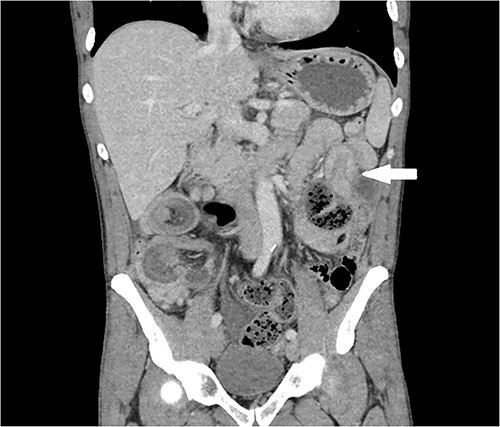

Computer-tomography (CT) demonstrated two points of synchronous intussusception. First, a relatively long segment ileocolic intussusception (Fig. 1) with dilated distal ileum containing faeculent matter, indicative of bowel obstruction. Second, a short segment small bowel intussusception involving jejunal loops (Fig. 2).

Coronal CT for abdomen and pelvis with portal venous contrast. Jejunal intussusception in left upper quadrant (white arrow).